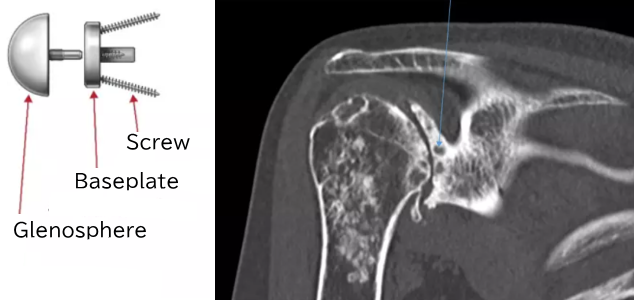

Normally, the baseplate is fixed to the glenoid with screws.

If the glenoid is deformed, the shape of the baseplate may not fit the glenoid properly.

Therefore, a shaped allograft is attached to the baseplate to fit the deformed glenoid.

The baseplate with the allograft is fixed to the glenoid.

The glenosphere is attached.